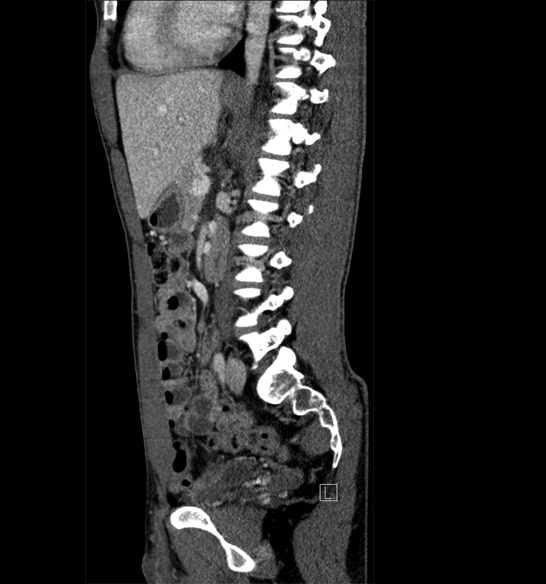

Body

Covers abdominal CT anatomy.